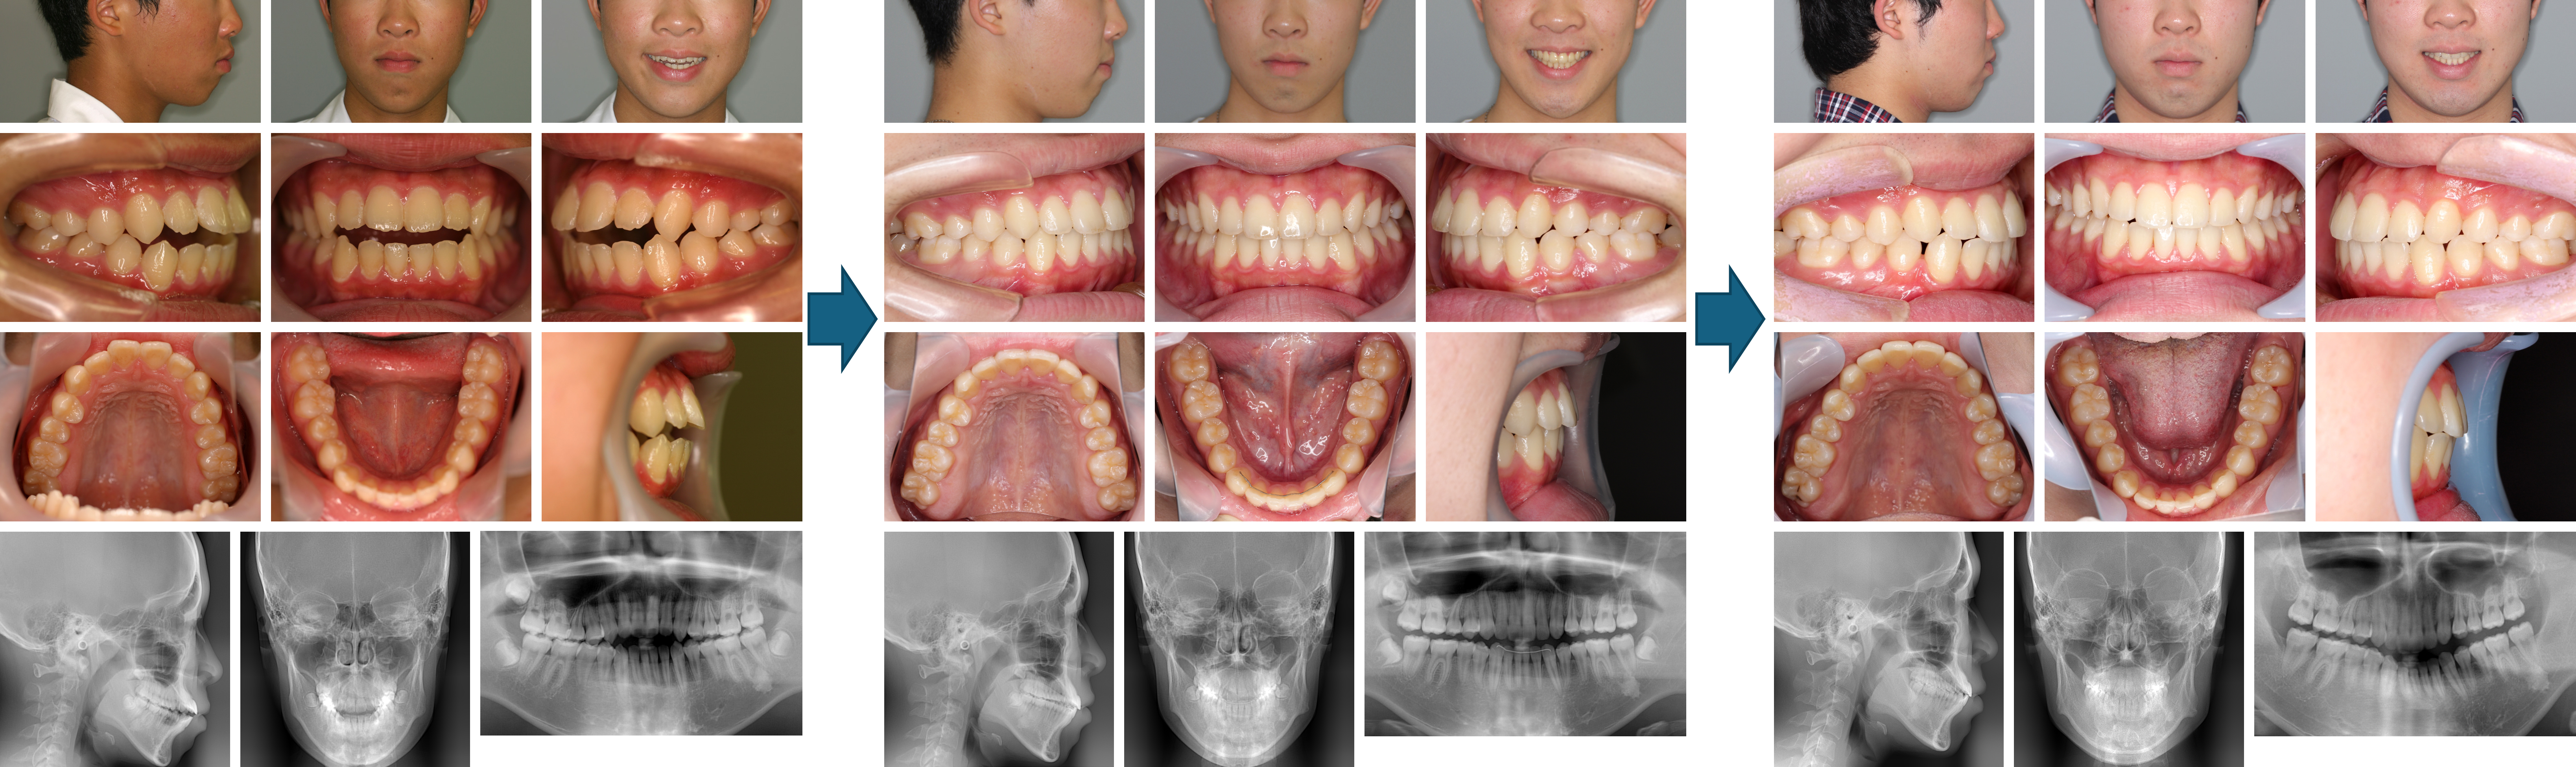

【治療例 K7719】初診時年齢:12歳1か月 / 性別:男性 / 主訴:出っ歯で口が閉じにくい

症例の概要:主訴は出っ歯で口が閉じにくい。サービカルヘッドギアと2×4装置にて上顎骨の成長抑制、下顎の成長促進を行った。さらにマルチブラケット装置にて緊密な咬合を獲得し、好ましい側貌を得ることが出来た。

主訴: 出っ歯で口が閉じにくい

診断名: 上顎前歯が唇側傾斜した上顎前突症例

使用した主な装置: マルチブラケット装置、サービカルヘットギア、歯肉切除

抜歯/非抜歯および抜歯部位: 非抜歯

治療期間:2年5か月

治療回数:25回